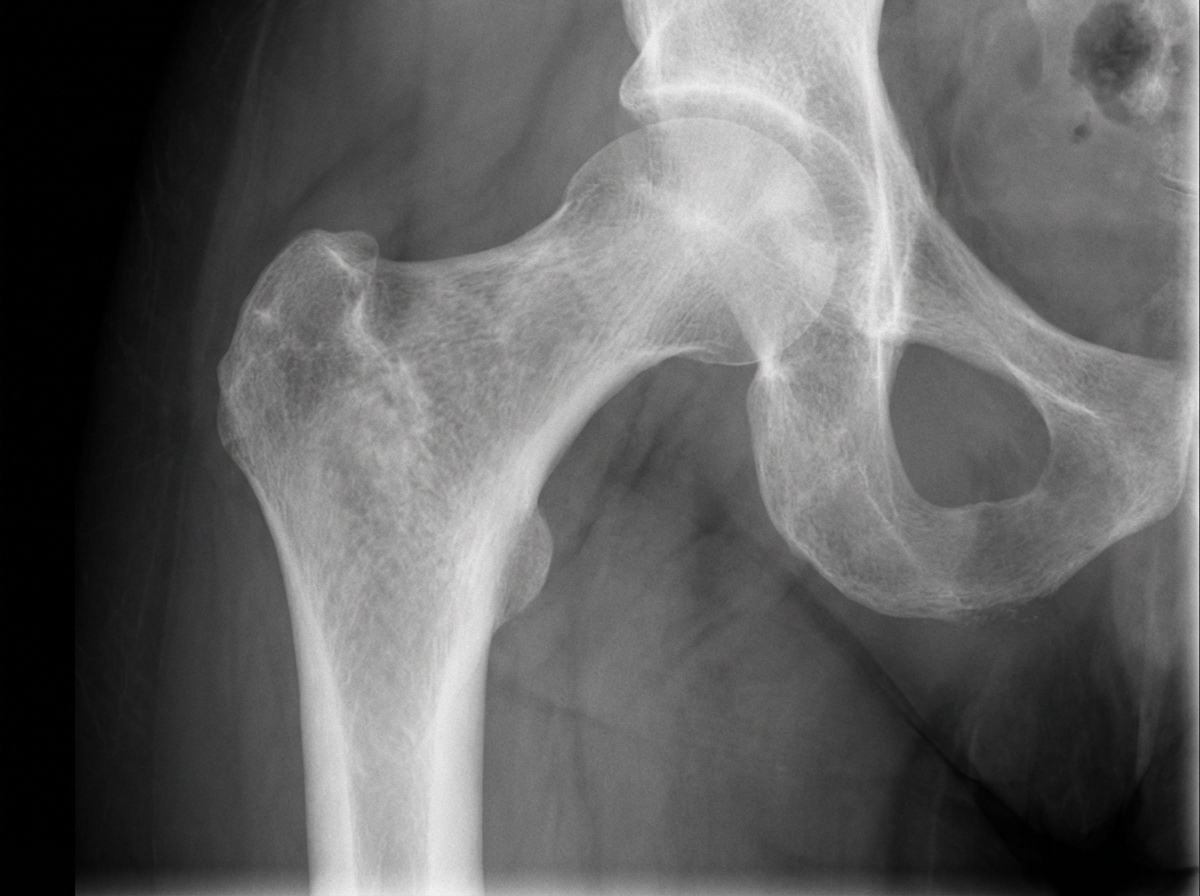

An X-ray of the proximal femur in a patient presenting with hip pain shows a specific deformity. What is this deformity?

Explanation: ***Shepherd crook deformity*** - Classic **coxa vara** deformity of the proximal femur seen in **fibrous dysplasia**, where the femoral neck bends downward resembling a shepherd's crook. - Results from **mechanical stress** on weakened bone filled with fibrous tissue, causing progressive **varus angulation** of the femoral neck. *Blade of grass deformity* - Characteristic radiological appearance of the **tibia** in **Paget's disease**, showing widened cortex and trabecular pattern. - Involves **long bones** like tibia and fibula, not typically the proximal femur as described in this case. *Chicken wire appearance* - Pathognomonic feature of **vertebral hemangiomas** showing coarse vertical trabeculae on lateral radiographs. - Specifically affects **vertebral bodies**, not the proximal femur or hip region. *Corduroy appearance* - Another radiological sign of **vertebral hemangiomas** seen on **frontal radiographs** showing vertical striations. - Limited to **spinal vertebrae** and does not involve the femoral neck or hip joint area.